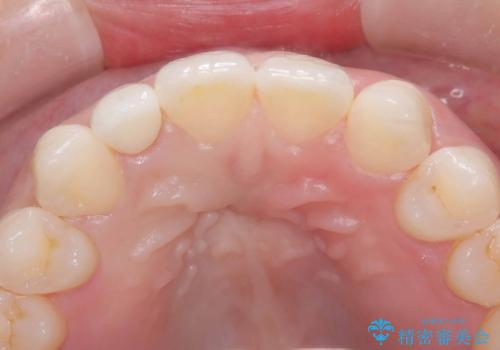

- 「前歯の見た目が気になる」を主訴に来院された患者様です。

右上2が矮小歯だったので、オールセラミッククラウンで審美修復しました。

見た目が改善され、大変ご満足いただけました。